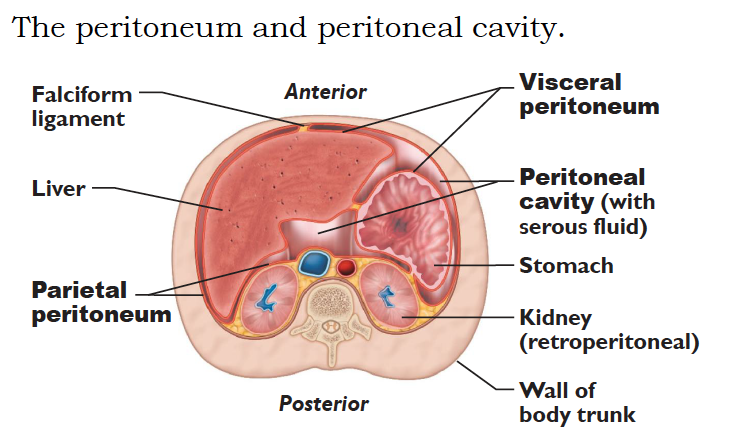

Serous membranes

...

2

Parietal Peritoneum

3

Dorsal Mesentery